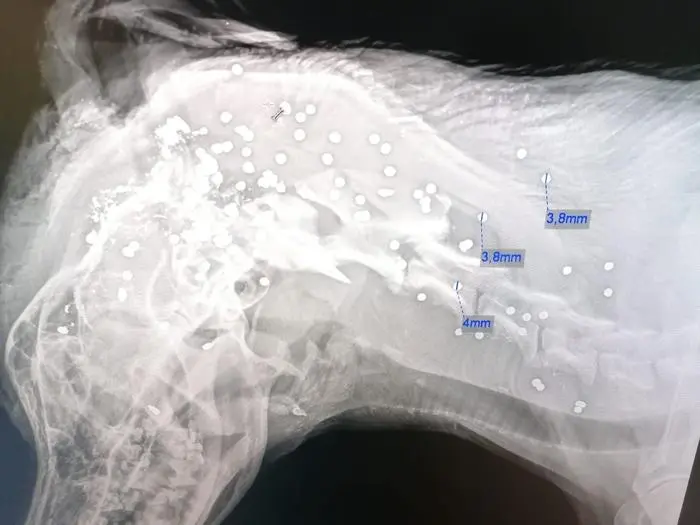

Am Montagabend erschoss ein Unbekannter den Hund der Familie der Landtagsabgeordneten und Bürgermeisterin von Fischbach, Silvia Karelly. Nach der Tat wurde das Tier in ein Bachbett geworfen. Es war nicht der erste Anschlag auf diesen Hund.

Der Pointer-Rüde Emil wurde am Montagabend erschossen